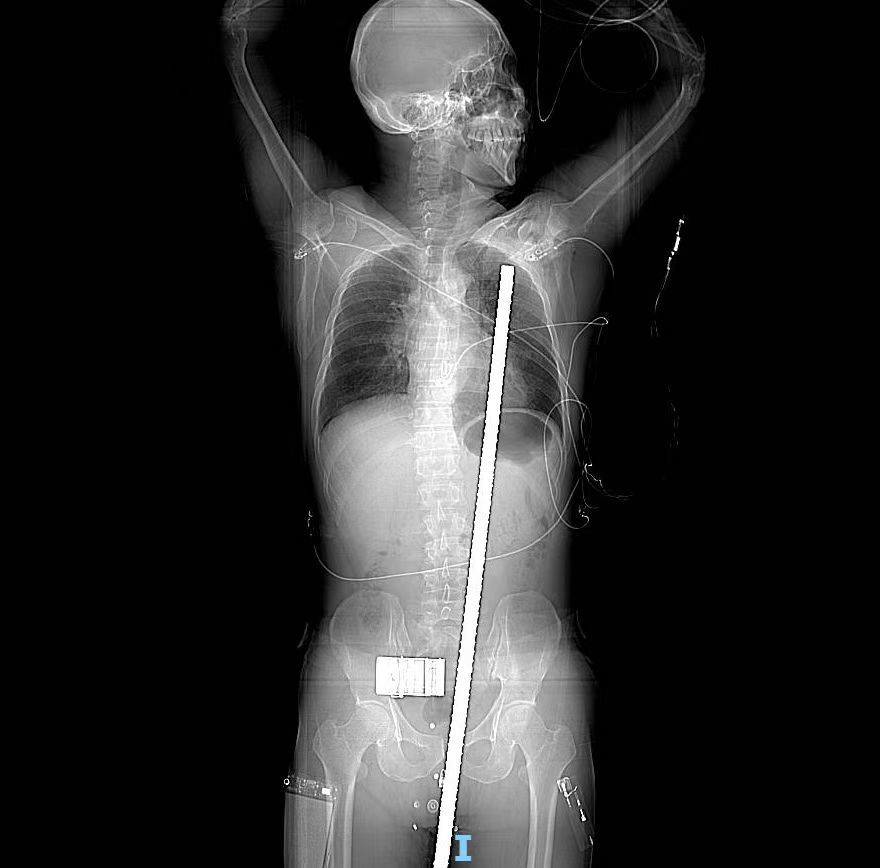

这根钢管长约60cm、直径3cm,直接贯穿患者整个胸腔、腹腔、盆腔,凶险程度可想而知!

当医护人员看到伤者的情况不由倒吸一口凉气,一根约60厘米长大拇指粗细的螺纹钢筋从男子会阴处插入,穿过腹腔、胸腔、盆腔,鲜血布满了患者全身。

经CT全面检查后,在场的医护人员都被患者的伤情所震惊,钢筋从右侧大腿根部进入身体,穿破膀胱、肠管、肠系膜、胃部、膈肌进入胸腔,直达左侧锁骨,离心脏及主动脉仅1cm。